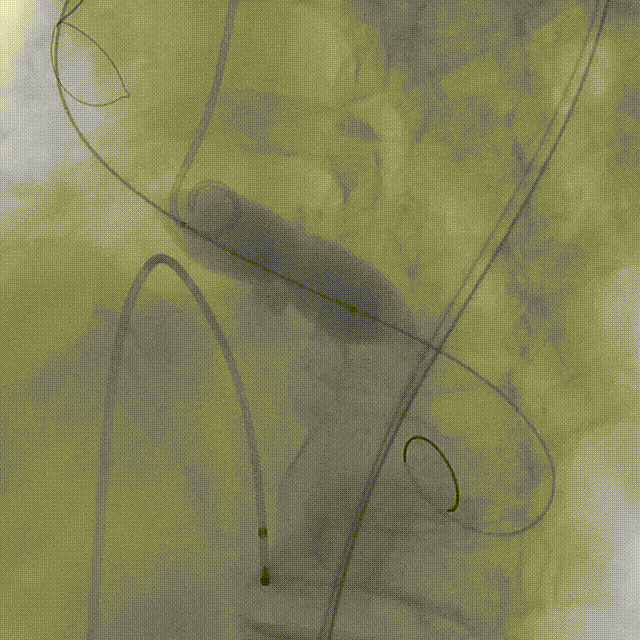

患者病史 主诉:发作性胸闷憋喘半年,加重伴呼吸困难2周。 现病史:患者半年前无明显诱因出现胸闷、憋喘,伴有下肢水肿,2周前上述症状明显加重,夜间不能平卧,痰中带血丝,为进一步诊治再次来我院,门诊以"心力衰竭"收入院。 既往史:肾功能不全、心房颤动 心脏超声提示:LVEF:0.54 1.主动脉瓣病变;2.主动脉瓣狭窄(重度)并反流(中度);3左室壁节段性运动不良;4.升主动脉扩张、双房扩大、左室肥厚;5.二尖瓣硬化并反流(中度);6.三尖瓣反流(轻-中度);7.肺动脉瓣反流;8.肺动脉高压(轻度)PGmean=105mmHg,Vmax=635cm/s,瓣口面积0.27cm²。 术前CT评估 Type0型二叶瓣,重度钙化,钙化集中在瓣叶游离缘,右冠窦为著;左冠高度11.8mm,由于左冠窦部空间较小,左冠风险较高, 升主动脉扩张,最宽处50.5mm;主动脉瓣环水平夹角61.5°,横位心。主动脉弓角77.6°,锐角弓,外周入路在腹主及髂总处有大量散状钙化,胸主处有81.6°的迂曲。 手术策略 推荐右侧股动脉为主入路,左侧股动脉为辅入路,送snare辅助过弯,使用18F大鞘,推荐预装ProStyle A® AV23瓣膜,20mm球囊预扩,初始定位对齐真实瓣环瓣上5mm超高位初始定位释放,释放过程中使瓣膜自然下滑,到工作位观察瓣膜形态,最终理想位置0-瓣下3mm。 手术过程 Step1:右侧股动脉为主入路、左侧股动脉为辅入路,成功穿刺并送入 18F 大鞘; Step2:主动脉根部造影,瓣口限制重 Step3:Type 0 型二叶瓣畸形合并重度钙化,患者瓣口狭窄严重,同时横位心,不仅导丝跨瓣困难,导管更难进入;术者凭借精湛操作,将导丝顺利跨瓣,反复微调导管角度,最终导管顺利过瓣。 导丝精准跨瓣 Step4:20mm球囊跨瓣困难,snare辅助下球囊成功跨瓣,预扩有腰无漏,冠脉充盈良好。 Step5: snare辅助下成功跨瓣,可以看到系统过弓形态瓣膜仓柔软,过弓顺滑 输送系统过弓 Step6:初始定位瓣上5mm开始释放,释放部分后观察瓣架下缘内收明显,后回收系统重新定位 初始定位 底部内收 Step7:瓣膜完全释放前,血压一度降低,术者迅速调整器械,实现瓣膜迅速锚定,快速释放 完全释放 Step8:20mm球囊后扩 最终造影,位置(瓣下3mm)形态良好 手术难点 患者不仅有主动脉瓣重度狭窄,还叠加肾功能不全、心房颤动等基础疾病,术中血流动力学波动极易引发心功能衰竭。ProStyle A® 预装干瓣“开包即用” 的特性压缩了术者操作时间,80%可回收设计给了术者容错空间,而这些看似难以逾越的难关,最终被团队精湛的医术一一化解,术中对于导丝、导管、球囊等器械每一步的精准操控,再到突发状况的从容处置,无不彰显着团队深厚的专业积淀与顶尖的操作技艺。 结语 此次手术的圆满成功,不仅彰显了陈玉国、李传保教授团队在复杂结构性心脏病介入治疗领域深厚的专业造诣与攻坚克难的决心,也充分验证了ProStyle A®系统在应对复杂高难度病例时的卓越适用性与有效性。 作为扎根齐鲁、享誉全国的医疗高地,山东大学齐鲁医院始终赓续着这片热土的仁厚文脉,将“医道从德,术业求精”的院训精神镌刻在每一次诊疗实践之中。特别是在结构性心脏病诊疗领域,医院团队始终怀揣医者担当,勇攀医学高峰,不断以更前沿的技术突破,为危重患者点亮重获新生的希望。 专家简介 陈玉国 山东大学齐鲁医院(点击查看专家详细简历) 李传保 山东大学齐鲁医院(点击查看专家详细简历) · END ·